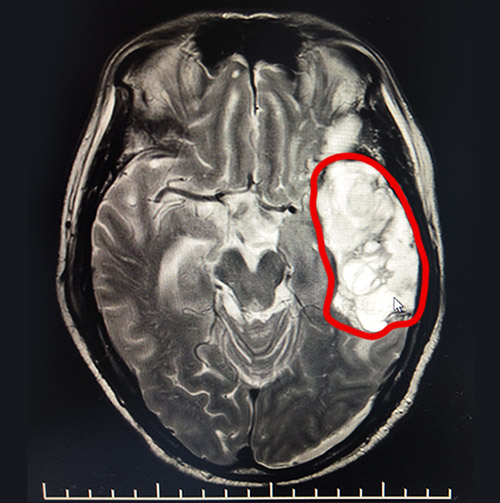

▲MRI影像显示,患者左侧额颞叶部较大面积血肿

在神经内科5病区,经验丰富的李振并主任详细了解了患者受伤和抢救的经过,在完善相关检查的基础上,给出了中西医结合和康复相辅相成的系统治疗方案。李振并主任表示,患者入院后的头颅影像检查显示,其左侧额颞叶出血虽正在慢慢吸收,但仍有较大面积的低密度灶,左侧脑室受压明显。为了加快血肿吸收速度,在通过药物降颅压的同时,营养患者的神经和脑细胞。